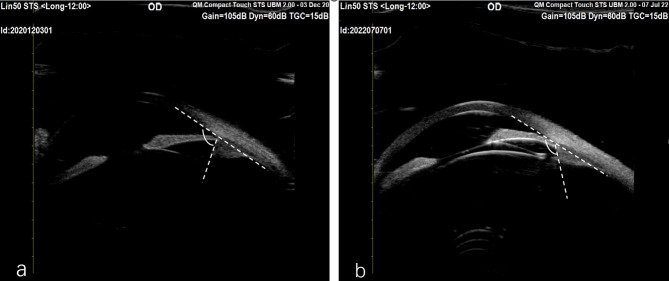

Case presentation: A 19-year-old woman with high myopia underwent bilateral TICL implantation. Preoperative imaging revealed shallow anterior chambers, high crystalline lens rise, small pupils in Pentacam HR (Oculus, Germany), and short ciliary processes in ultrasound biomicroscopy (UBM). Both eyes developed low postoperative vaults. Nineteen months later, she returned with bilateral 0 μm vault and anterior subcapsular cataracts. Repeat UBM confirmed short ciliary processes and partial footplate slippage beneath the ciliary sulcus. The left TICL was replaced with a larger lens, but 0 μm vault recurred. The right eye was monitored without further intervention.